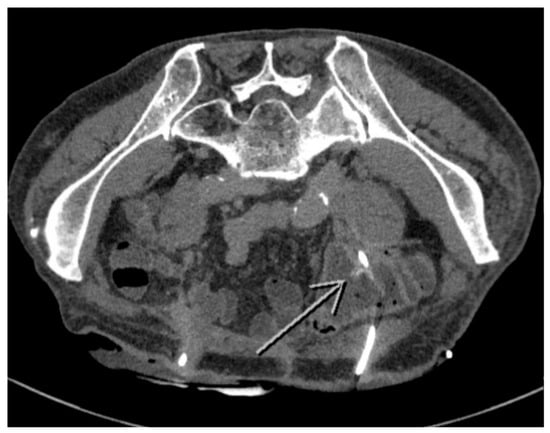

2. Case Presentation

2.2. Treatment

2.3. Outcome and Follow-Up